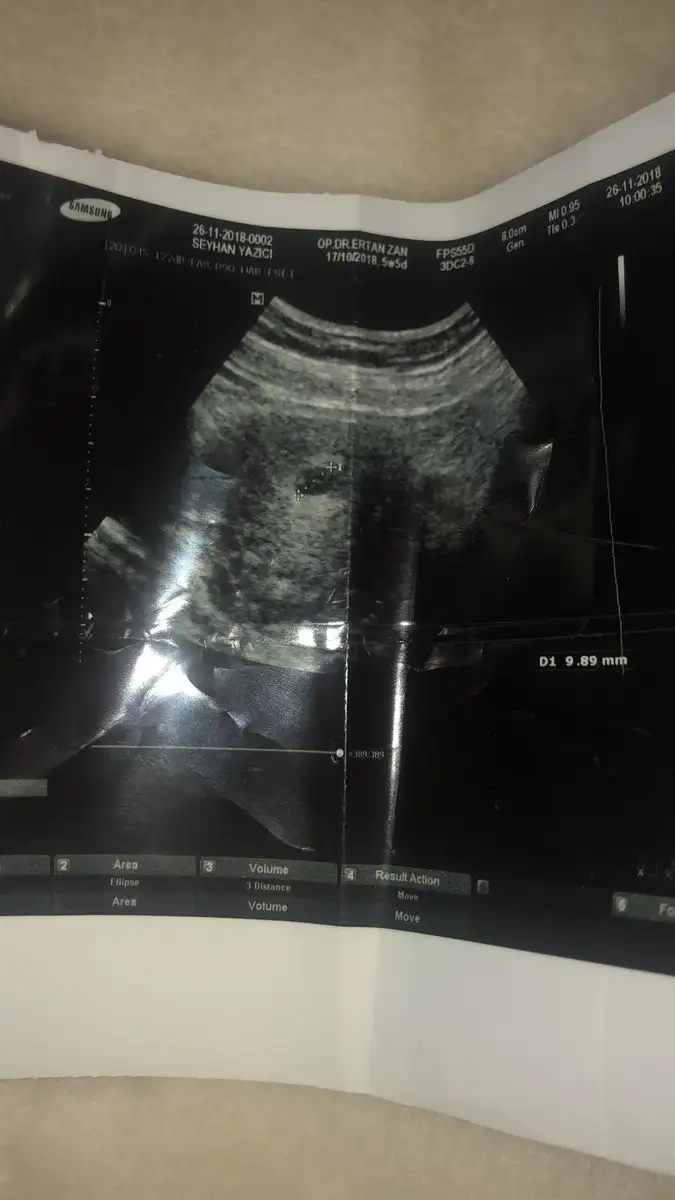

Eklentiler

• E22C90E0-7991-4CE7-8475-44C069F68F25.webp

E22C90E0-7991-4CE7-8475-44C069F68F25.webp

25,7 KB · Görüntüleme: 28